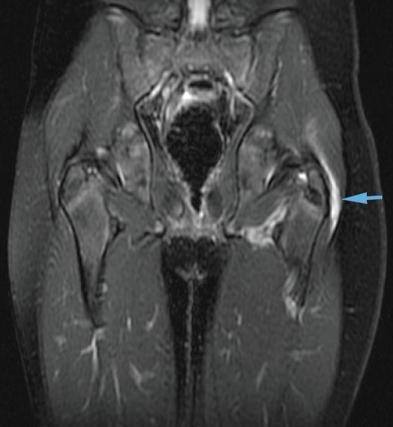

This is inflammation of the trochanteric bursa.

This bursa is at the top, outer side of the femur. It has the function of working as a shock absorber and as a lubricant for the movement of the muscles adjacent to it, especially the Ilio-Tibial Band (ITB). This is a strong sheet of tissue that runs from the Pelvis all the way past the knee to insert into the Tibia.

The ITB can get tight over time or due to general deconditioning and poor gait. The ITB will cause friction over the Trochanteric Prominence causing the Bursa to get inflamed.